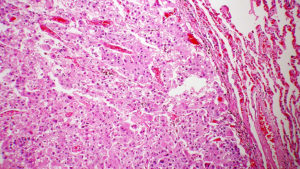

Come l’infiammazione cronica promuove il cancro al fegato